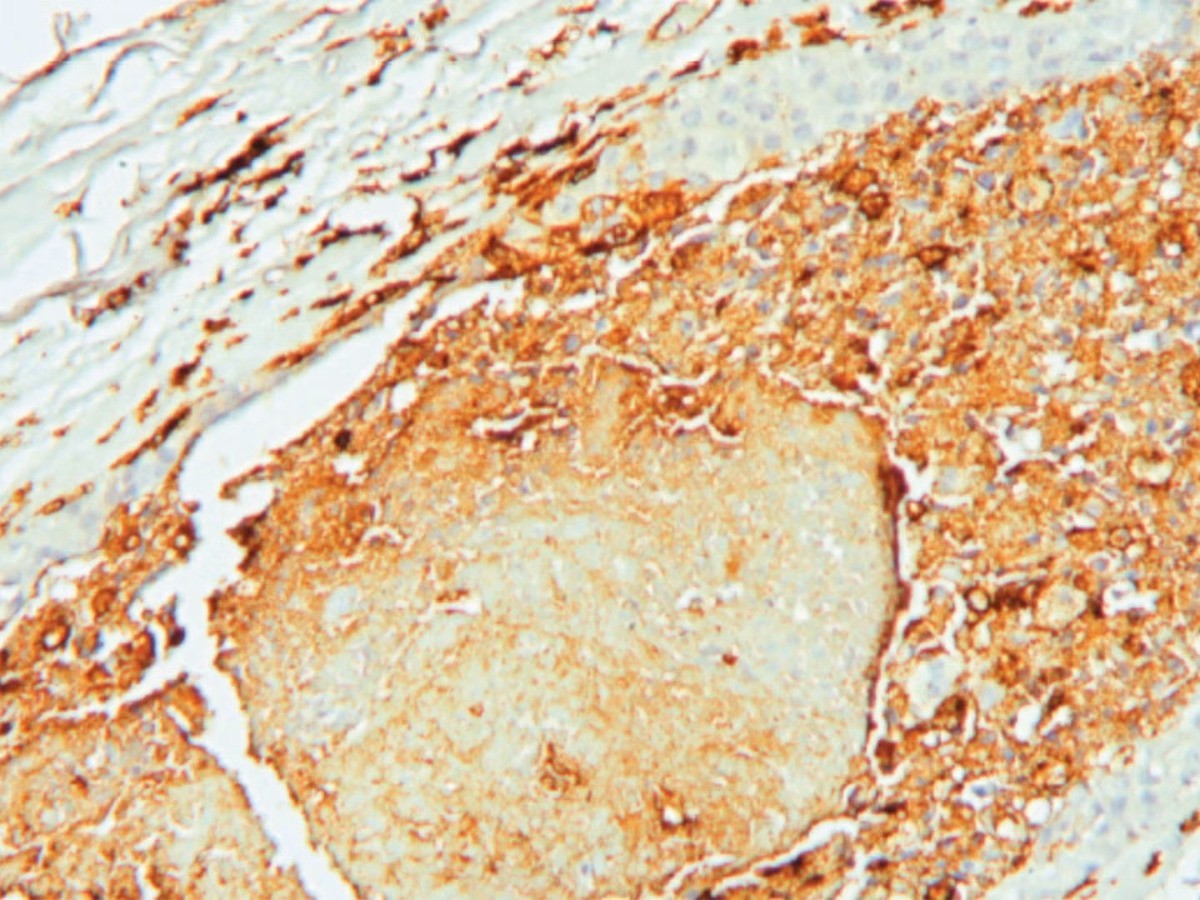

واعتمدت الدراسة، المنشورة في دورية Cell Reports Medicine، على تحليل أكثر من 300 عينة لمرضى مصابين بابيضاض الدم النقوي الحاد، إضافة إلى تجارب أجريت على أنسجة بشرية ونماذج فئران مزروعة بخلايا لوكيميا بشرية.

لم تتوقف الدراسة عند التحليل المختبري، بل امتدت إلى اختبار التركيبة على نماذج فئران زرعت بخلايا خلايا ابيضاض الدم النقوي الحاد بشرية، تحمل طفرات جينية معروفة بتسببها في مقاومة "فينيتوكلاكس".

في هذا النموذج، لم ينجح "فينيتوكلاكس" وحده في إطالة عمر الفئران إطلاقاً، كما كان الباحثون يتوقعون، بناء على التركيب الجيني للخلايا. لكن عند استخدام التركيبة، عاش معظم الفئران 11 إلى 12 شهراً، بل إن أحدها كان لا يزال على قيد الحياة عند انتهاء الدراسة.

وتعد هذه النتائج استثنائية، في مجال أبحاث سرطان خلايا "ابيضاض الدم النقوي الحاد"، حيث غالباً ما تكون الفائدة العلاجية محدودة في النماذج التي تمثل حالات مقاومة شديدة.